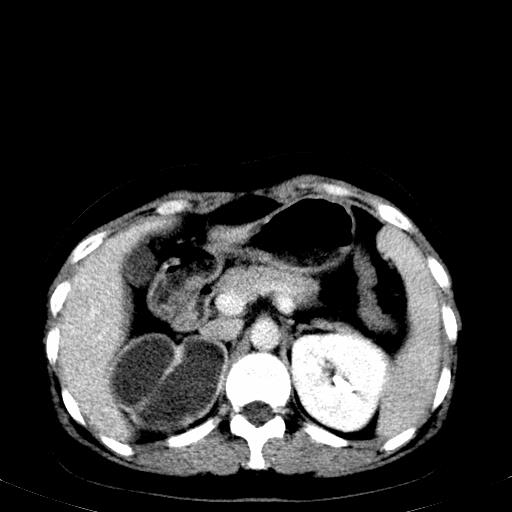

右肾多发囊肿,左肾、左输尿管结石

右侧肾积水、左侧肾结石

右侧肾积水、左侧肾结石  ,要排除右肾结核可能。

右侧肾积水、左侧肾结石 ,原因待查

1)不排除右肾结核可能。2)左肾及左输尿管上段结石?

左肾哪里有结石???

第一个序列应该是延迟图像吧;

结合强化图片看ivp意义不大,建议作逆行造影看一下;

左肾不是结石,是造影后改变.右肾积水,功能仅存.